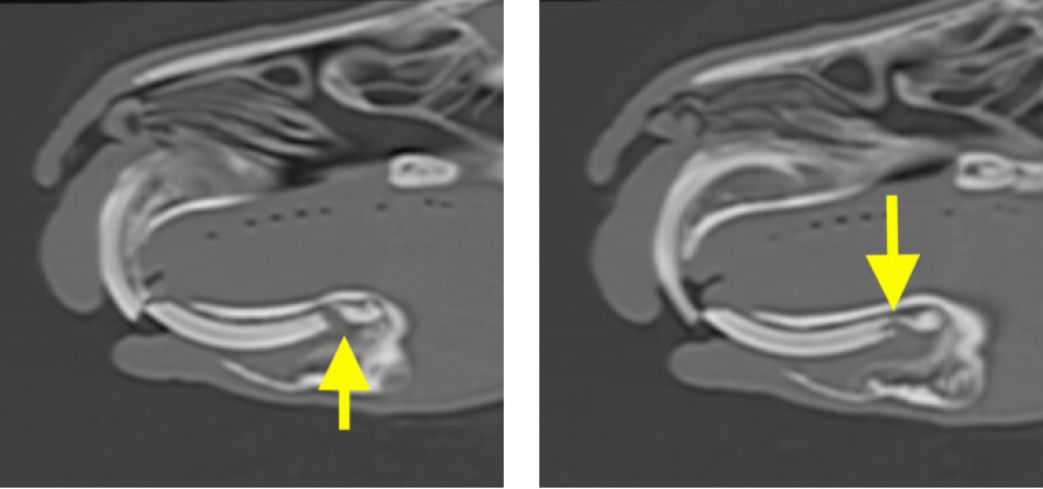

L’esame TAC rappresenta ormai il gold standard per la valutazione delle patologie del cavo orale di conigli e piccoli roditori (cavie, cincillà…). Per le caratteristiche particolari dei loro denti, infatti, conigli e piccoli roditori sono predisposti a problemi di malocclusione, allungamento dentale, ascessi e fratture. In tutte queste situazioni, la TAC garantisce la massima precisione diagnostica, più accurata di quanto si riesca ad ottenere dalle tradizionali radiografie. La possibilità di ricostruzione in 3D in corso di patologia dentale, inoltre, rappresenta un valido aiuto pre-operatorio per programmare un intervento dentale.